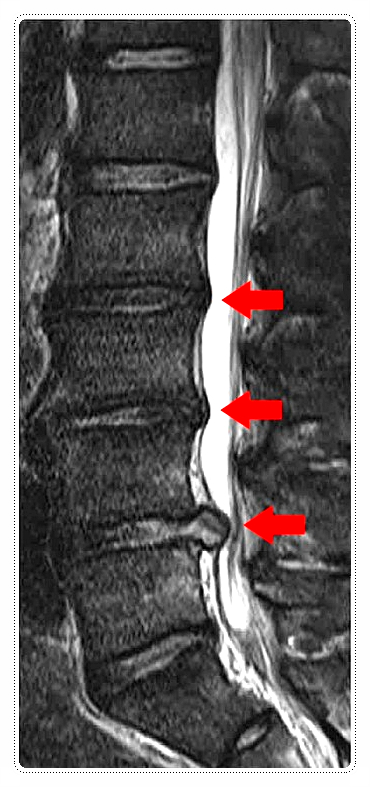

허리 디스크가 제 위치에서 벗어나면 주변 신경을 자극하게 됩니다.

이 신경은 허리뿐 아니라 엉덩이, 꼬리뼈, 다리까지 이어지는데요.

그래서 어떤 분들은 “통증은 허리에서 오는 것 같은데 꼬리뼈가 더 아프다”라고 느끼기도 합니다.